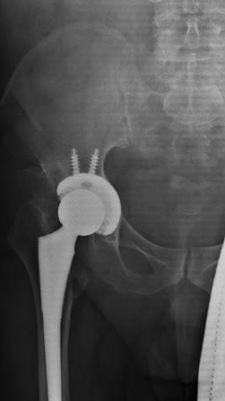

Total Hip Replacement of Ball and Socket